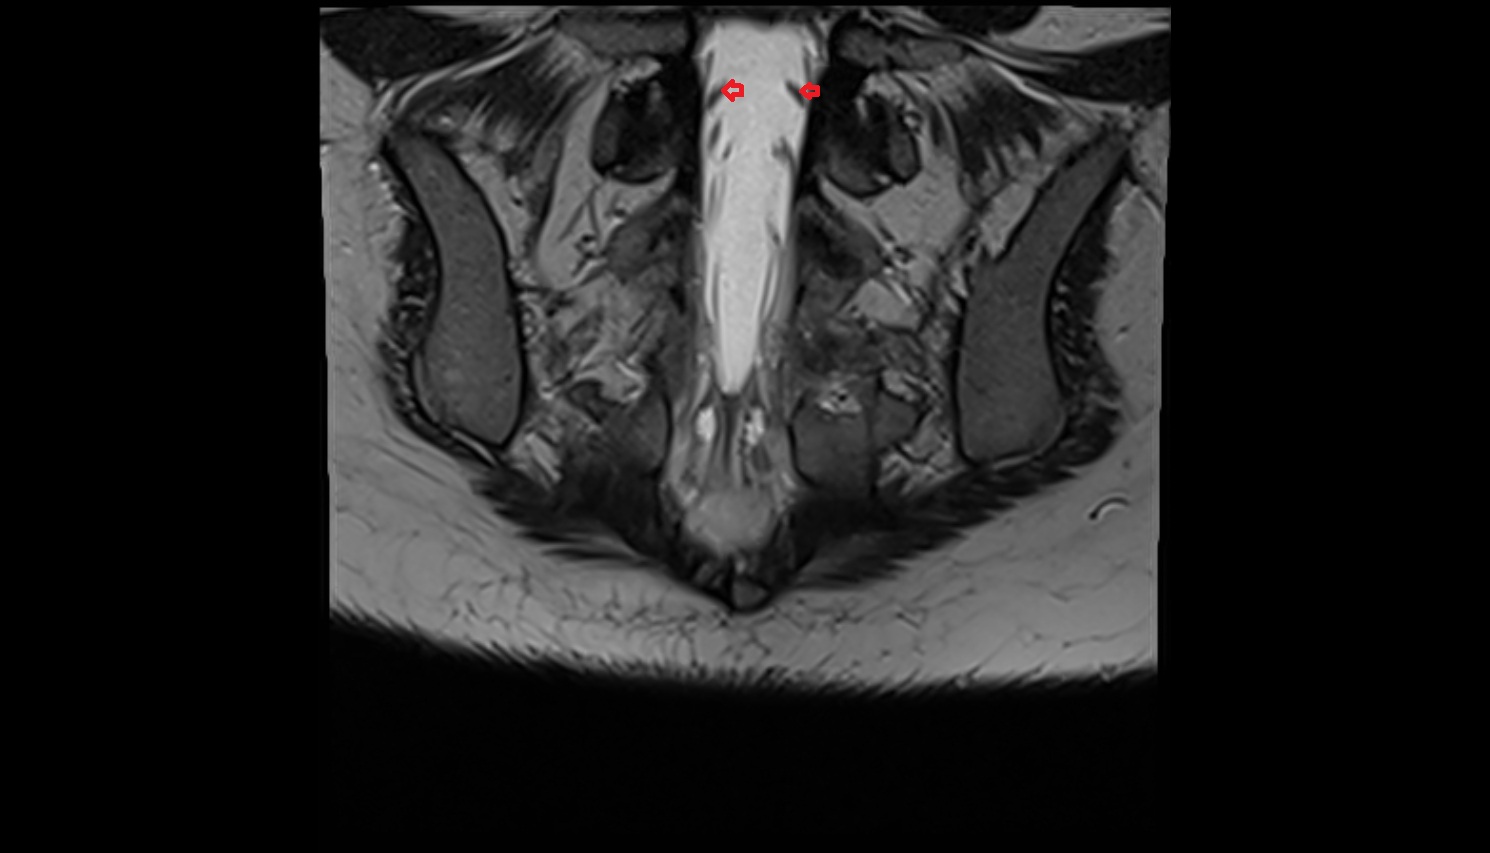

- Peripheral zone of prostate

- Anterior Fibromuscular Stroma of prostate

- Central zone of prostate

- Transitional zone of prostate